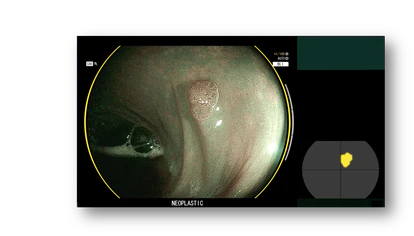

“Hasta ahora, el conocimiento médico y científico se basaba en registrar datos clínicos de pacientes, analizarlos con los métodos estadísticos tradicionales que conocíamos para descubrir qué factores y variables eran importantes, y así construir patrones. Esa información ya la teníamos, pero no la sabíamos explotar lo suficiente. La IA abre una puerta de un mundo de extracción de datos, de creación de patrones muy detallados, y aplicarlos a los pacientes”, detalla Puig, que ha publicado numerosos estudios al respecto y ha participado como coautor en las recomendaciones internacionales de la Sociedad Europea de Endoscopia Digestiva. Él trabaja con CAD EYE, una función para la detección de pólipos de colon desarrollada por Fujifilm. “Tengo la suerte de disponer de esta herramienta que tiene dos finalidades: ayudar a detectar pólipos , mediante la observación de su superficie, establecer de qué tipo es. ¿Cómo se ha desarrollado? Entrenándola con miles de vídeos y enseñando al software qué es y qué no es un pólipo. De esa forma se ha construido un patrón de reconocimiento”.

Una de sus grandes ventajas es la capacidad de mantener la atención en todo momento y reforzar el trabajo del especialista. “Este sistema no sustituye al médico, pero es de gran ayuda porque le alerta. Los médicos somos humanos y no podemos mantener la atención al 100% en todo momento. Incluso al endoscopista más experto se le pasan aproximadamente un 10% de los pólipos que, afortunadamente son los más pequeños y la mayoría no degeneran. El CAD EYE nos alerta, señalándolo con un cuadrado azul. Otras veces, nos sirve para contrastar. Podemos ver algo que parece un pólipo pero no estar seguros, normalmente contrastamos con compañeros, pero de esta manera tienes a otro experto a tu lado”.

Gracias a esta herramienta, el especialista no solo detecta con mayor precisión y eficacia estos pólipos, sino que también determina de manera inmediata su tipología. “De esta manera podemos dejar los pólipos benignos, y los que son extraídos ya no es necesario analizarlos porque ya tenemos ese diagnóstico gracias a la IA. Esto representa una gran mejora en el proceso: cuando termina la colonoscopia ya podemos hacer las recomendaciones al paciente sin esperar al resultado de una biopsia”.